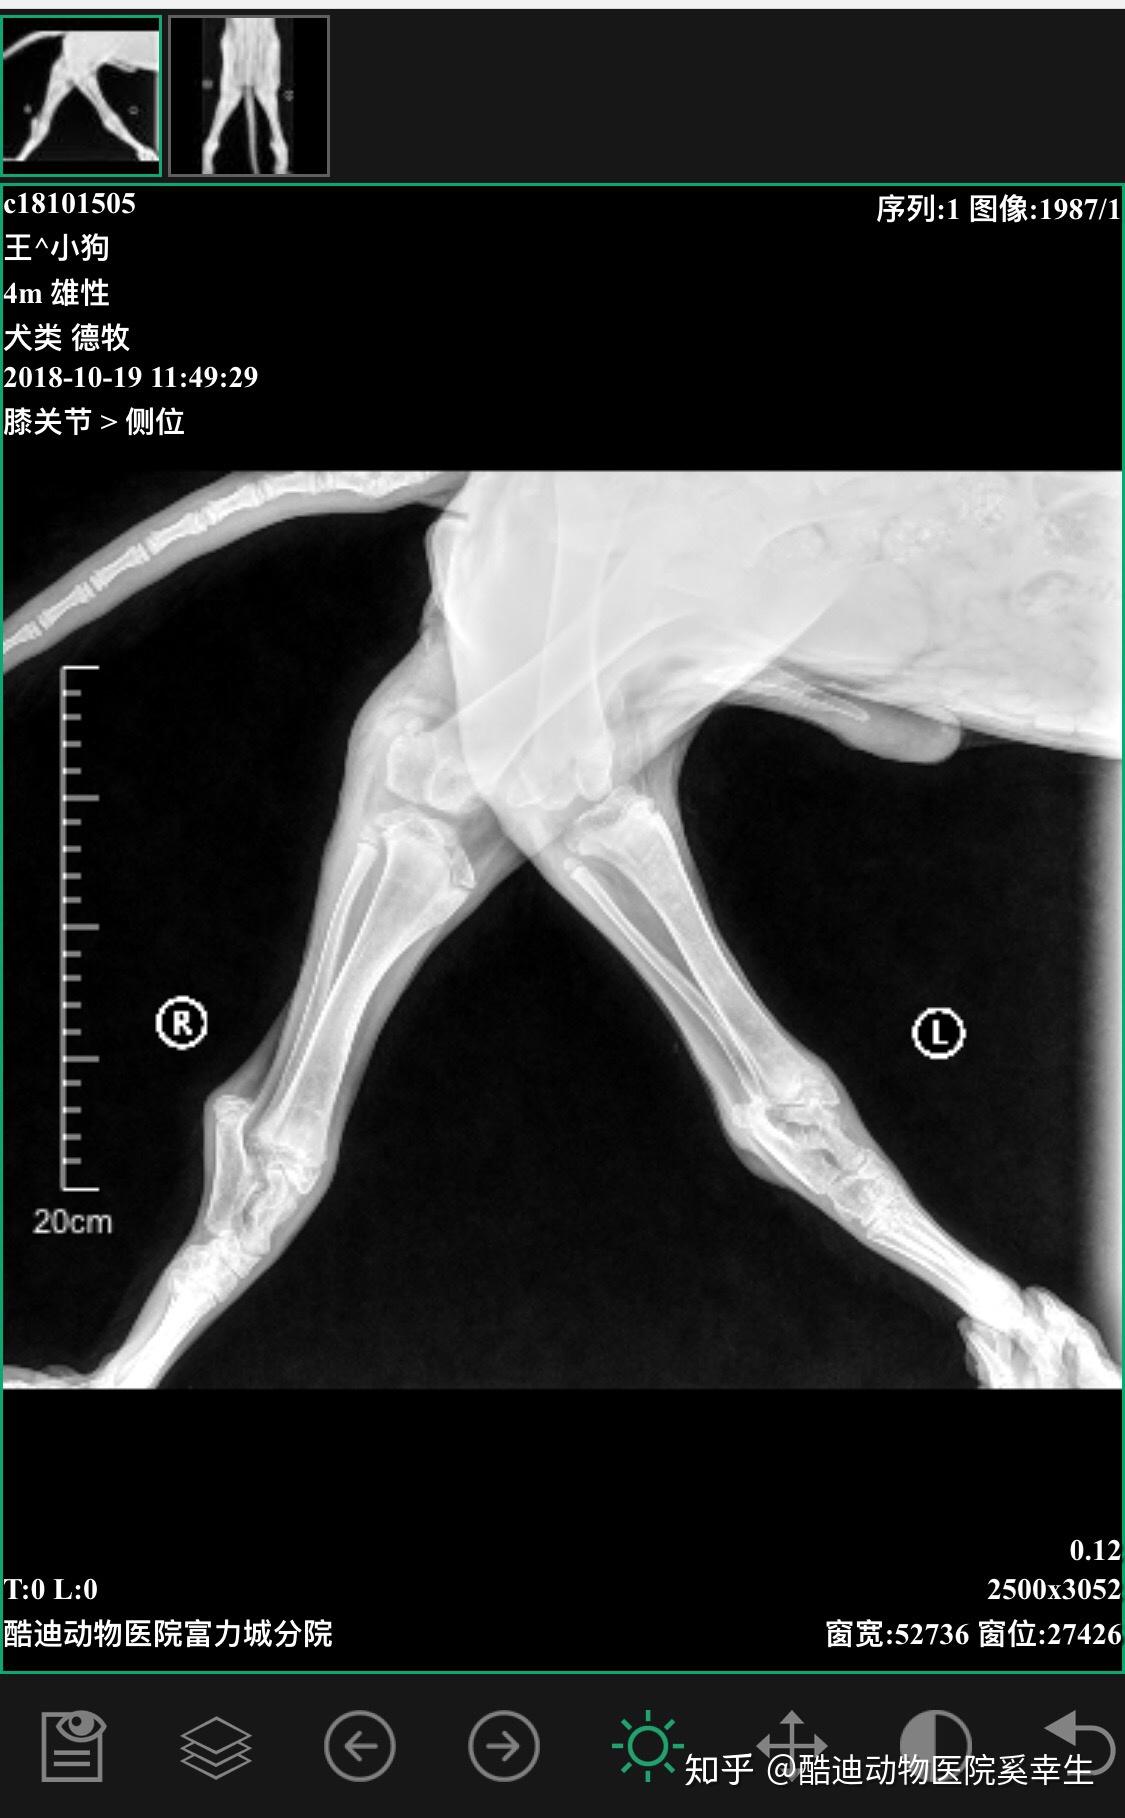

犬科动物没有反关节!

图片尺寸641x360